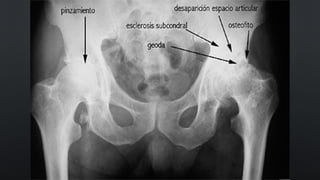

RADIOLOGÍA

¿COMO SOLICITAR LAS

PLACAS?

• RX DE PELVIS AP Y DE CADERAS EN ABDUCCIÓN

• RX DE RODILLA DE PIE AP-L Y AXIAL DE ROTULA

( EN CARGA)

• OTROS ESTUDIOS COMPLEMENTARIOS:

ARTROCENTESIS, ESTUDIO BIOQUÍMICO

SIGNOS

• DISMINUCIÓN DEL ESPACIO ARTICULAR

• ESCLEROSIS SUBCONDRAL

• OSTEOFITOS

• QUISTES SUBCONDRALES

RADIOLOGÍA ¿COMO SOLICITAR LAS PLACAS? •RX DE PELVIS AP Y DE CADERAS EN ABDUCCIÓN • RX DE RODILLA DE PIE AP-L Y AXIAL DE ROTULA ( EN CARGA) • OTROS ESTUDIOS COMPLEMENTARIOS: ARTROCENTESIS, ESTUDIO BIOQUÍMICO SIGNOS • DISMINUCIÓN DEL ESPACIO ARTICULAR • ESCLEROSIS SUBCONDRAL • OSTEOFITOS • QUISTES SUBCONDRALES